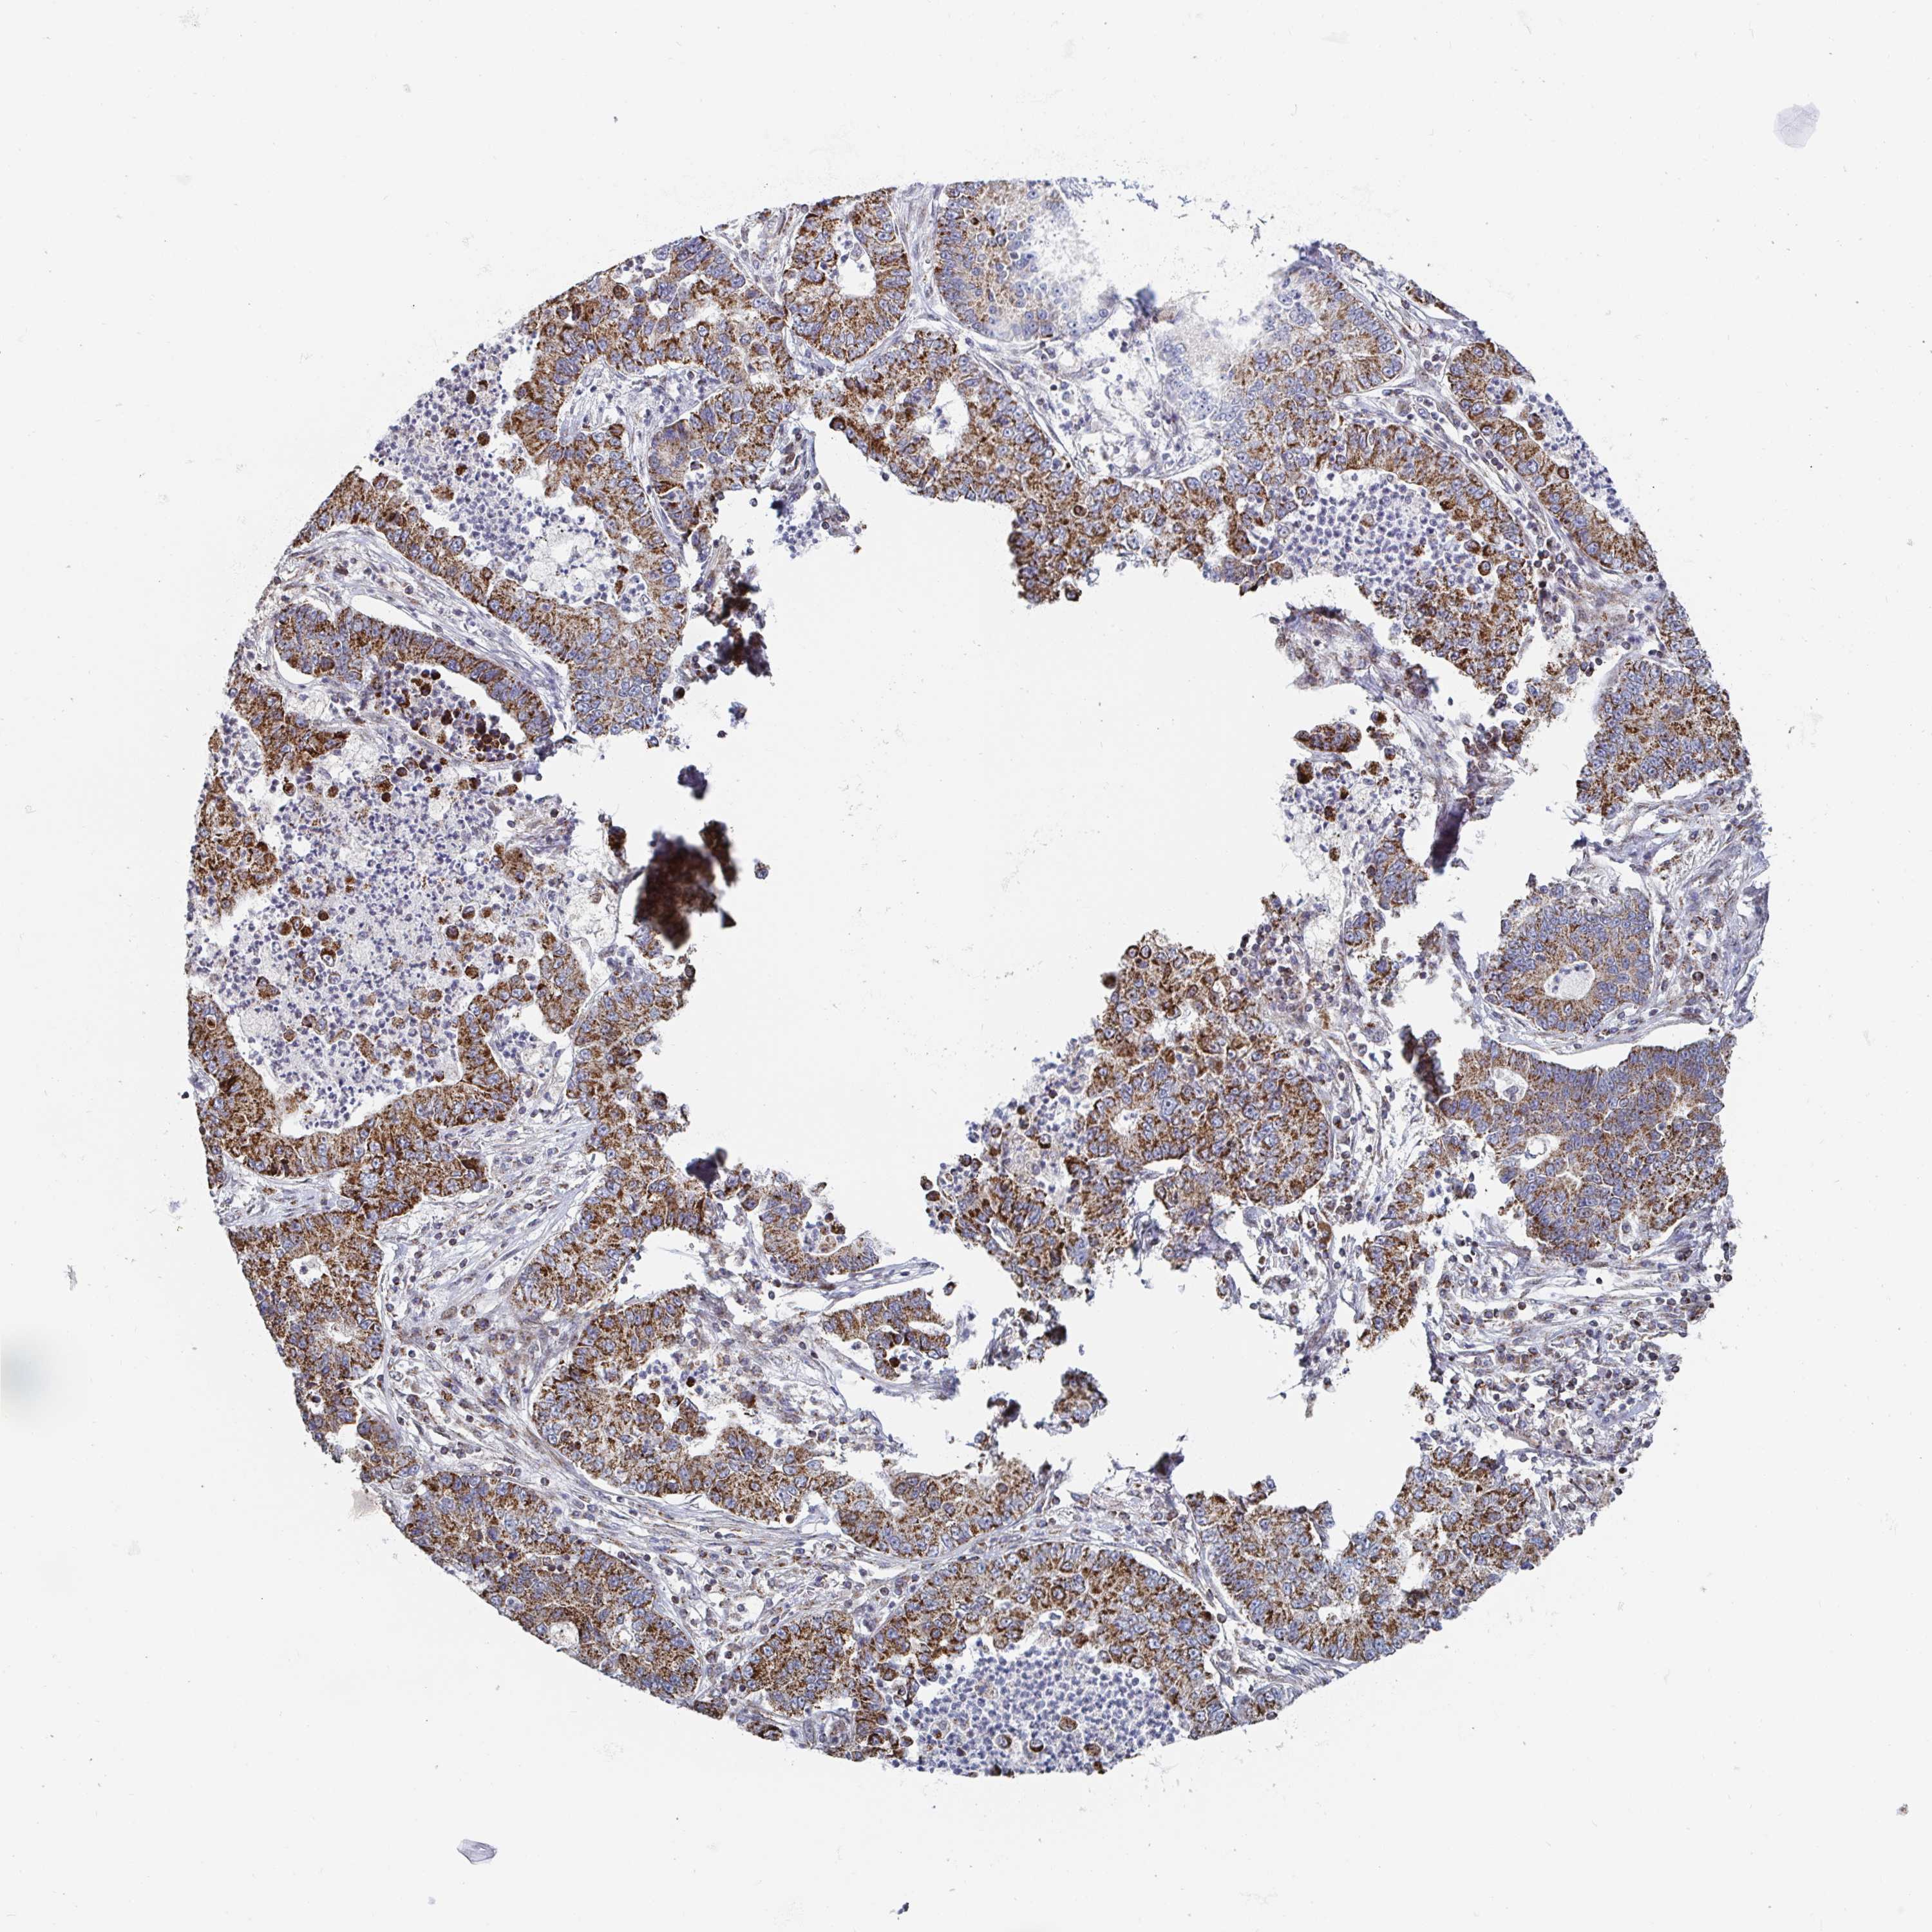

CANCER LUNG CANCER Show tissue menu

Lung cancer

Human cancer

Lung adenocarcinoma

Lung squamous cell carcinoma